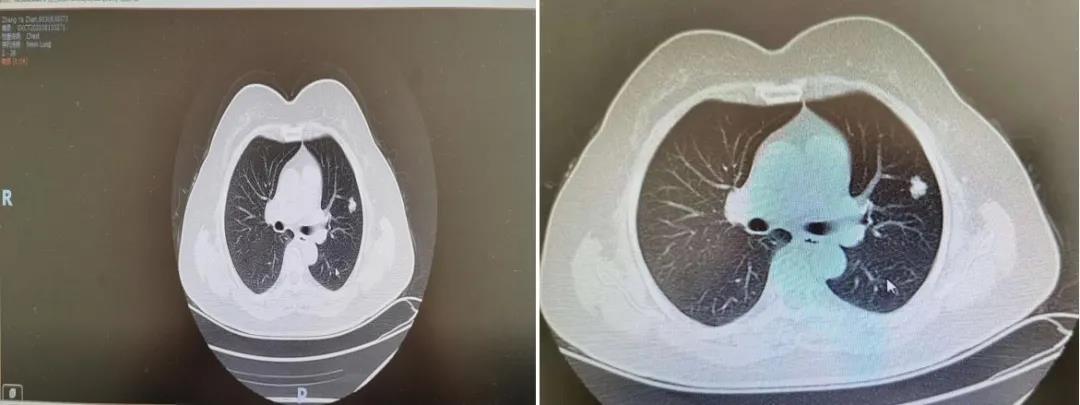

这天上午的时间对于李冰来说,过得有些慢,不时的看着表,怎么张女士还没有到,是否又不来了呢?正在李冰有些焦虑的时候,“哪位是李冰?我是张某某,来做肺CT的”,“来了来了,张阿姨来了”,李冰快乐的像个孩子,赶紧找到体检中心副主任刘彦玲,安排张女士复筛肺CT,果不出所料,张女士的肺CT有一个结节,体检中心的所有人员和李冰一样,心里一沉,体检中心的刘主任赶紧通过绿色通道,预约医院肺小结节多学科MDT会诊,并和家属联系,让其周二来医院会诊。可是,周二的早晨,没能等来张女士前来会诊,李冰和刘主任一样,内心似五味杂陈,说不出来的滋味。不能放弃!刘主任要到了张女士女儿的电话号码,电话拨出去了,所有的人都紧张的不敢喘气,能否前来就诊呢?这不只是挽救一个生命,更是幸福一个家庭呀!滴滴滴滴滴……,“您好……”电话那边终于有了回复,患者的女儿说母亲因为恐惧,不敢前来,让其父亲来会诊,在多学科会诊室,专家团队仔细分析肺部结节的性质,大小,有毛刺,有凹陷症,有血管,专家们耐心的和患者家属进行沟通,“患者的诊断考虑为早期肺癌,建议尽快手术治疗,可以达到治愈,如果再发现晚一些,可能就没有手术机会了。”患者家属仿佛抓到了救命的稻草一样,在狂风暴雨和无尽的黑暗中看见一丝光明……正是因为这样一群具有责任心的专家、健康守卫者,正是因为这样一个具有实力的、勇敢的、冲锋在抗癌一线的医疗战队,也正是因为这样一所温暖的、充满爱的医院,在生命最后的防线上,保障了每一个家庭的幸福生活。